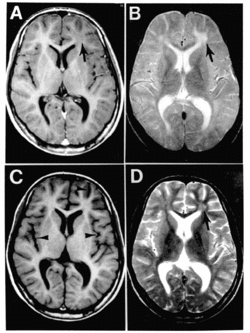

Die Entzündung des Gehirns und seiner Häute (Meningoenzephalitis) ist selten (bei 0,1 % der Erkrankungen), verläuft jedoch in 10–20 % der Fälle tödlich. In weiteren 20–30 % bleiben dauerhafte Schädigungen des Gehirns zurück.[92]

Die Meningoenzephalitis kann sich vier bis sieben Tage[92] nach Exanthembeginn entwickeln, bei Patienten über sechs Jahren häufiger als bei Kleinkindern. Sie manifestiert sich mit Fieber, Kopfschmerz, meningealer Reizung (Nackensteifigkeit, Erbrechen) sowie Bewusstseinsstörungen bis zum Koma. Schwere Verlaufsformen äußern sich in epileptischen Anfällen und anderen neurologischen Funktionsstörungen. Bei der Lumbalpunktion zeigt das gewonnene Hirnwasser eine Zellvermehrung (Pleozytose) und eine erhöhte Proteinkonzentration. Nach Einführung der Masernimpfung sank das Vorkommen der durch Masern ausgelösten Meningoenzephalitis kontinuierlich und liegt in Deutschland bei weniger als zehn Fällen im Jahr.

Bei Kindern mit angeborenen oder erworbenen Immundefekten kann es in seltenen Fällen zu einer besonderen Form der Gehirnentzündung durch Masernviren kommen („Einschlusskörperchenenzephalitis“, measles inclusion-body encephalitis, MIBE, von englisch measles für „Masern“). Diese Komplikation manifestiert sich meist innerhalb eines Jahres nach Maserninfektion mit schwer behandelbaren fokalen Krampfanfällen und endet in der Regel innerhalb von wenigen Monaten tödlich.[100] Die Diagnose kann durch eine Gewebeprobeentnahme aus dem Gehirn (Biopsie) gestellt werden. Es sind auch Fälle beschrieben worden, die durch das Impfvirus verursacht wurden.[101] Menschen mit bestimmten schweren angeborenen oder erworbenen Immundefekten dürfen daher nicht gegen Masern geimpft werden.[92]

Subakute sklerosierende Panenzephalitis

Die subakute sklerosierende Panenzephalitis (SSPE) ist eine Spätkomplikation nach Maserninfektion, die eine generalisierte Entzündung des Gehirns mit Nerven-Entmarkung (Demyelinisierung) und schwersten Schäden nach sich zieht und in mehr als 95 % der Fälle tödlich endet.[102] Die Entstehung der SSPE ist nicht vollständig geklärt. Eine Rolle scheinen dabei Mutationen der Proteine der Virushülle zu spielen, insbesondere bei den Aminosäuren an den Positionen 64 (Pro), 89 (Glu) und 209 (Ala) des M-Proteins (sogenanntes PEA-Motiv).[96][103][104] Gerade das Ala209 ist für eine gesteigerte Virenausbreitung innerhalb des Körpers verantwortlich. In Impfviren sowie Laborstämmen tritt dieses Motiv nicht auf, an den jeweiligen Positionen wurden folgende Aminosäuren identifiziert: Ser, Lys bzw. Thr (sog. SKT-Motiv).[103][105] Dies könnte erklären, warum man in Gewebeproben SSPE-infizierter Gehirne ausschließlich Masern-Wildviren nachgewiesen hat und nicht Masern-Impfviren; außerdem gibt es keine Evidenzen dafür, dass eine Masernimpfung eine SSPE verursachen oder beschleunigen könnte.[106][105]

Die Erkrankung tritt Monate bis zehn Jahre nach einer Maserninfektion auf, im Durchschnitt nach sieben Jahren. Der Verlauf ist langsam progredient über ein bis drei Jahre – die SSPE zählt zu den sog. Slow Virus Infections. In jeweils 10 % der Fälle tritt ein akuter, schnellerer (3 bis 6 Monate) oder ein langsamerer Verlauf (länger als drei Jahre) auf.

Es lassen sich vier Stadien der SSPE abgrenzen.[105] Das erste Stadium ist durch Reizbarkeit, Demenz, Lethargie, Sprachstörungen und Rückgang sozialer Interaktionen gekennzeichnet, das zweite durch Störungen der Motorik wie Dyskinesie, Dystonie und Muskelkrämpfe (Myoklonien). Im dritten Stadium manifestieren sich ein extrapyramidales Syndrom, spastische Lähmungen sowie ein Dezerebrationssyndrom, bei dem das Großhirn stark geschädigt ist. Im EEG finden sich typische Veränderungen, die wegweisend für die SSPE sind (Radermecker-Komplex). Im letzten Stadium kommt es zu Funktionsausfällen der Großhirnrinde, was zu einem Wachkoma, einem akinetischen Mutismus, dem Ausfall vegetativer Funktionen (wie z. B. Atmung, Puls, Blutdruck) und schließlich zum Tode führt.